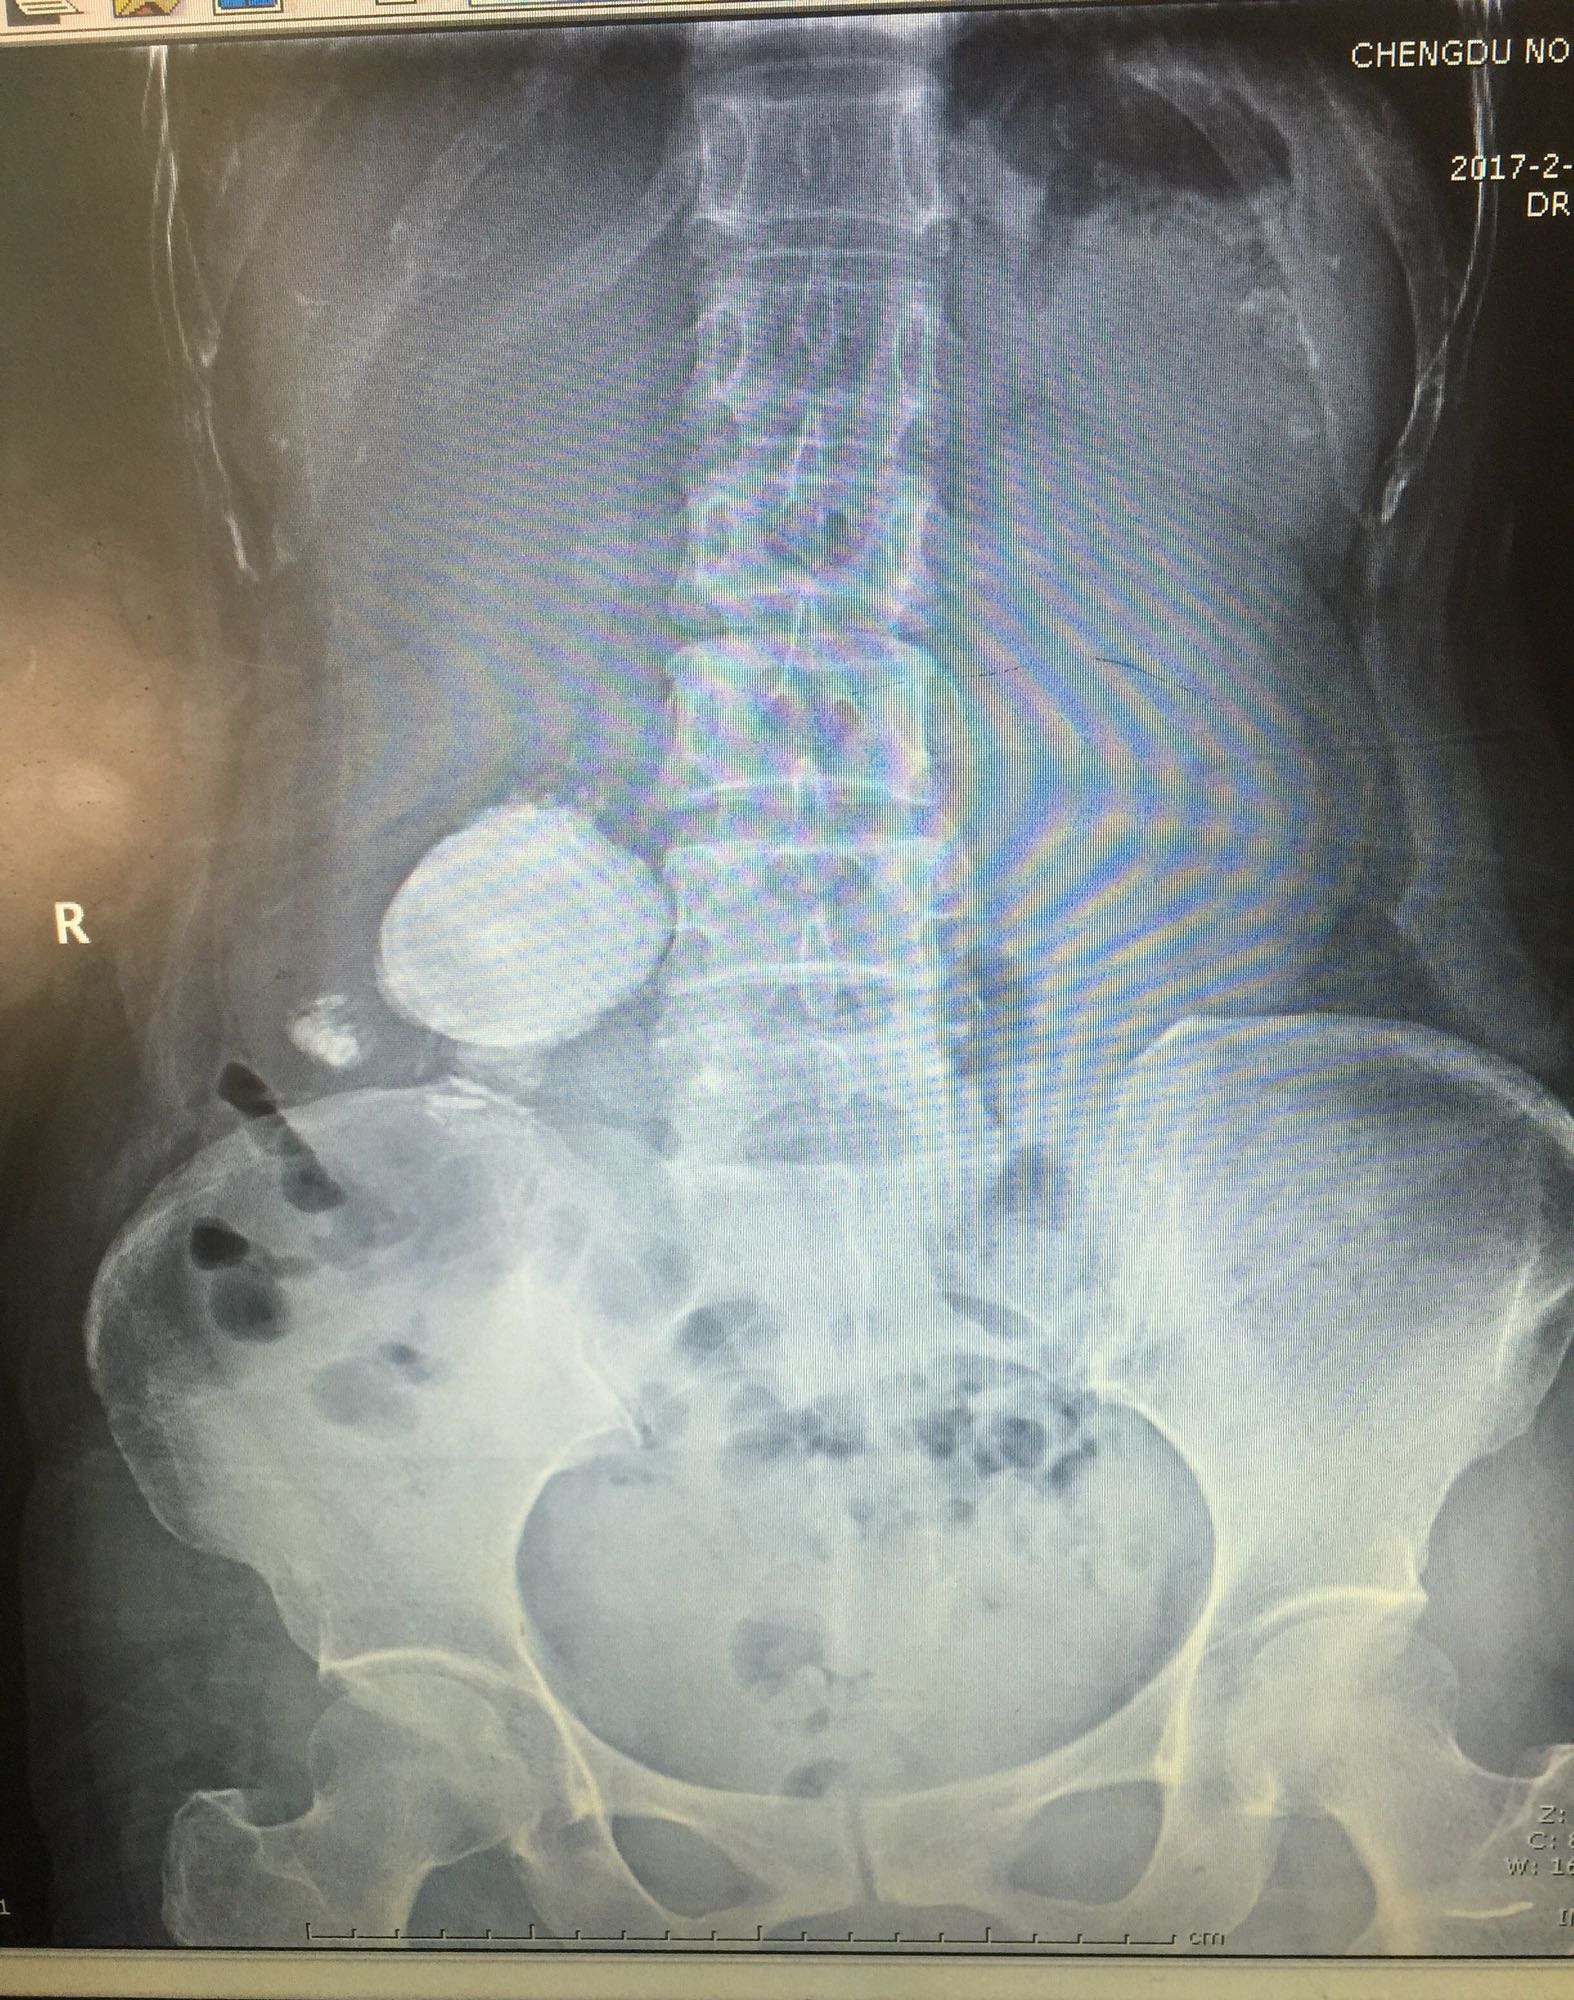

右侧肾脏巨大铸型结石一例

肾盂积水伴输尿管肾盂连接处梗阻 肾结石

60余岁老年男性 因右侧腰痛伴发热1周入院 1周前开始出现右侧腰部胀痛,伴低热,无尿频尿急及肉眼血尿,无其他不适症状 既往高血压,无糖尿病及其他病史

查体右侧肾区轻度叩痛,余症状阴性 辅助检查尿白细胞+++,肾功正常,甲状旁腺激素正常,钙磷比例正常范围

右侧肾脏巨大铸型结石,右肾盂输尿管连接部狭窄? 拟完善GFR测定后决定下一步治疗方案,目前倾向于开放手术。

该患者结石大,且负荷大部分位于肾盂,肾盂几乎被填满,所以考虑是否有右侧输尿管肾盂连接部狭窄可能,结石负荷大,结合上述情况可行开放手术,一期整形 。 但若为UPJO,患者肾脏积水轻,肾脏皮质厚,肾功影响小,可能性相对小。行PCN结合超声吸附,一期清理肾盂内结石应该问题不大。 对于该患者的治疗,不知大家意见如何?